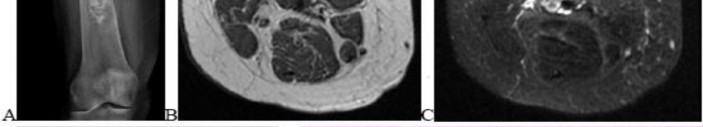

A 15-year-old male presents with deep knee pain awakening him at night. Radiographs show a permeative destructive lesion in the distal femoral metaphysis with a 'sunburst' periosteal reaction and Codman's triangle.

Biopsy confirms high-grade conventional osteosarcoma. What is the most critical prognostic factor for long-term overall survival in this patient?

Explanation

For localized high-grade osteosarcoma, the most important prognostic indicator is the histologic response to neoadjuvant chemotherapy. This is evaluated during the definitive resection. A 'good response' is typically defined as greater than 90% or 99% tumor necrosis. Patients who achieve this level of necrosis have a significantly improved disease-free and overall survival rate compared to 'poor responders' who have extensive viable tumor cells remaining.